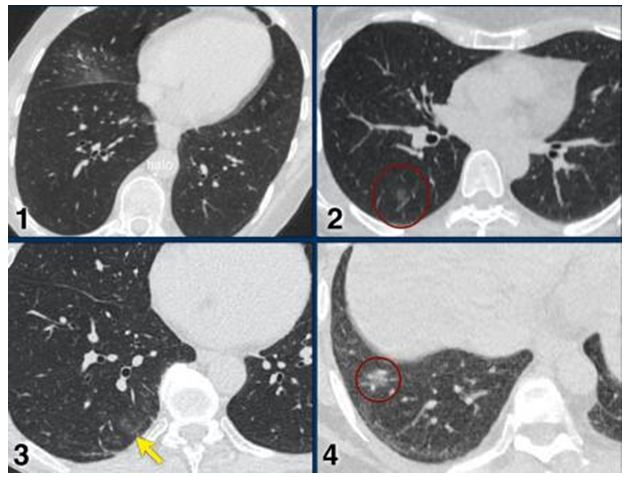

CO-RADS 2: Hình 2 – 3 – 4

Hình 2: Hình ảnh tổn thương CT: “Tree-in-bub sign” vùng ngoại vi phân thùy sau dưới bên phải, giãn & dầy nhẹ thành phế quản vùng trung tâm thùy dưới phổi trái. Không thấy tổn thương GGO. (Tổn thương giống viêm phế quản hơn COVID 19)

Hình 3: Hình ảnh tổn thương CT bao gồm giãn & dầy nhẹ thành phế quản, “tree-in-bub sign” & hình đông đặc. Không thấy tổn thương GGO.

Hình 4: Hình ảnh tổn thương CT bao gồm đông đặc thùy phổi & “tree-in-bub sign” (mũi tên). BN bị viêm phổi do nhiễm khuẩn lan tràn theo đường phế quản (dấu hiệu búp cây).